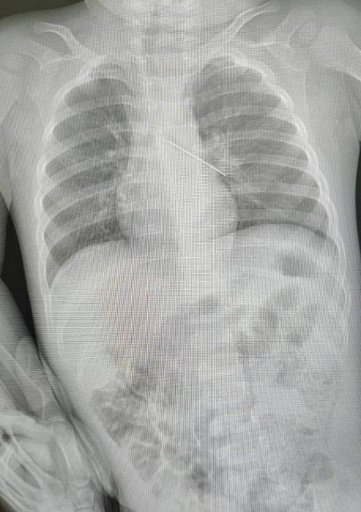

В Сургуте врачи Центра охраны материнства и детства спасли малыша, вытащив из его бронхов проглоченную трехсантиметровую булавку. Об этом случае рассказал директор депздрава Югры Роман Паськов.

Ребенок не мог дышать. Как показало быстрое обследование, булавка прошла по горлу и трахее, попав в бронхи и застряв там. Ситуация угрожала жизни ребенка.

«В клинику экстренно доставили малыша — 1 год и 5 месяцев. Ребёнок проглотил английскую булавку. Мама очень быстро среагировала, сразу привезла сына в больницу — и именно это помогло выиграть драгоценное время. После обследования специалисты увидели, что булавка оказалась в бронхах — ситуация, которая всегда несёт реальную угрозу жизни».

Вытащили булавку довольно быстро с помощью бронхоскопа. Если бы эта операция провалилась, ребенка пришлось бы вскрывать хирургическим путем.